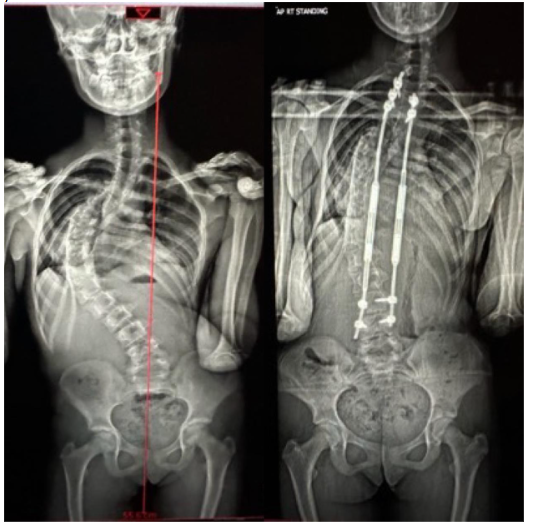

We conducted a retrospective study of all surgically managed patients with idiopathic EOS with age at diagnosis <10 years of age. All the patients included in the study had growing rods inserted when the cobbs angle reached more than 50 degrees and were progressive with growth. These patients had a trial of casting under GA/bracing to control the curve progression when the age at diagnosis was less than 5 years of age. Those who failed conservative management were subsequently included for the insertion of growing rods. The study was conducted between the time period of 2016-2018 with a minimum of 2-year follow-up. Overall, 28 patients had underwent growing rods insertion for EOS at Alder Hey NHS Children’s Hospital, Liverpool, United Kingdom. The patients were treated surgically with standard insertion of growth rods (traditional/MCGR) at the stable/neutral vertebrae depending on the curve pattern and magnitude of the scoliotic curve. Out of 28 patients, only 17 had a idiopathic condition. The rest of the 11 patients were neuromuscular, syndromic and congenital hence they were excluded from the study. Demographics, radiological parameters and pulmonary function tests were observed and compared. The spirometry was done for all surgically planned patients pre-operatively and around 2 years post-operative period. The spirometry was done by the senior respiratory technician after adequate instructions to the children as per standard protocol. The test itself was repeated for 3 times to check the adequacy and repeatability of the acquired respiratory loops and curves. The quality was in turn graded from A to E (best to no acceptable loops). The tests were accepted only when the quality of the curves was adequate and repeatable. Out of 17, only 8 patients had a reproducible and acceptable pre- and post-operative pulmonary function test. The rest of the 9 patients had either just a post-operative PFTs or could not adequately perform PFTs pre-operatively and hence were excluded. All the patients included in the study during this time period had Magnetic Controlled Growing Rods (MCGR) inserted. The MCGR were sequentially distracted remotely under ultrasound guidance every 3 months by a specialist nurse/consultant. Post-op X-rays were taken to observe the height gain after each distraction along with implant status. The FEV1 and FVC were measured pre- and post-operatively, and the age predicted percentage values were calculated using the Stanojevic equations and Global Lung function Initiative (GLI 2012). The GLI provides reference values for lung function indices calculated with spirometry such as FEV1, FVC, FEV1/FVC, FEF25%, FEF 75% etc among others. The reference values are age, sex and height dependent and hence measured prior to the test pre- and post-op. The Upper and Lower Limits of Normal (ULN and LLN) were noted based on the reference values for a particular age, sex and height. The z score change of FEV1 and FVC pre- and post-operatively were calculated to indicate decline/improvement in lung functions. Z-score indicates how many standard deviations a measurement is from its predicted value usually mean +/- 2 SD. A value of LLN -1.64 is considered as a cut off to indicate presence of lung function decline in patients for that particular age, sex and height. Z scores were calculated pre- and post-operatively independently from the GLI reference values and the change in values were also measured and analysed. The Cobbs angle and T1-T12 height were calculated pre-op, post-op and at 2 years follow up using whole spine standing X rays or low radiation EOS images. The pattern of respiratory outcome was also analysed pre- and post-operatively. Non-parametric correlations(r) between %predicted values, z score changes and cobbs angle change, thoracic height gain over a period of 2 years were studied to assess if lung functions improved with increase in T1-T12 height or correction of cobb’s angle. Throughout the analysis, p<0.05 is considered statistically significant and r values were calculated for correlation analysis (r>0.5).Results

Eight patients, who had a reproducible respiratory function test, were included in the study (2 male, 6 female). 3 patients had age at diagnosis < 3 years of age and were given a trial of casting/bracing. 5 patients were < 10 years of age and were monitored every 6 months with radiological and clinical assessment to review the progression of the curve with a spinal brace. The patients were offered surgical management with growing rods once the cobbs angle reached > 50 degrees and pre-pubertal/Rissers grade 0 with atleast more than 2 years of growth left.